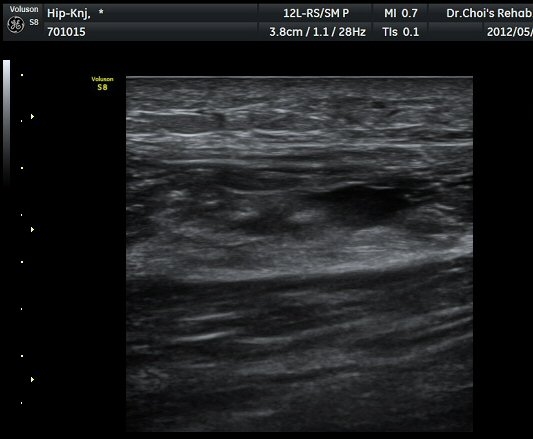

ŽÃËÀÚ¸¦ ¾Æ·¡·Î À̵¿ÇÏ´Ï ´ëÅðÁ÷±Ù³»¿¡ Àú¿¡ÄÚ º¯º¯ÀÌ °üÂûµÈ´Ù(±×¸² 2, 3).

´ëÅðÁ÷±Ù Á¾´Ü¸é°Ë»ç¿¡¼­ ±ÙÀ°³»¿¡ ¼±»óÀÇ Àú¿¡ÄÚ °¢±ØÀÌ °üÂûµÈ´Ù(±×¸² 4, 5).